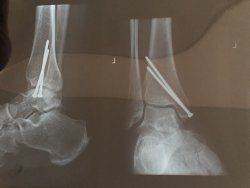

They can compare xrays at KULDo we need a 'how much metal in my body' thread?![]()